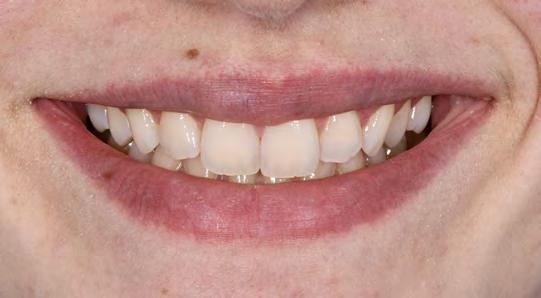

97 96 ESTETICA FUNZIONE POSTURA 145 _ Profilo sinistro con sorriso. 146 _ Ripresa di 3/4 sinistra con sorriso. 147 _ Immagine frontale naturale, senza sorriso. 148 _ Immagine frontale con sorriso. 149 _ Ripresa di 3/4 destra con sorriso. 150 _ Profilo destro (senza) con sorriso. 151 _ Dettaglio del sorriso. 152 _ Dettaglio del sorriso nel profilo destro. 153 _ Dettaglio del sorriso nel profilo sinistro.